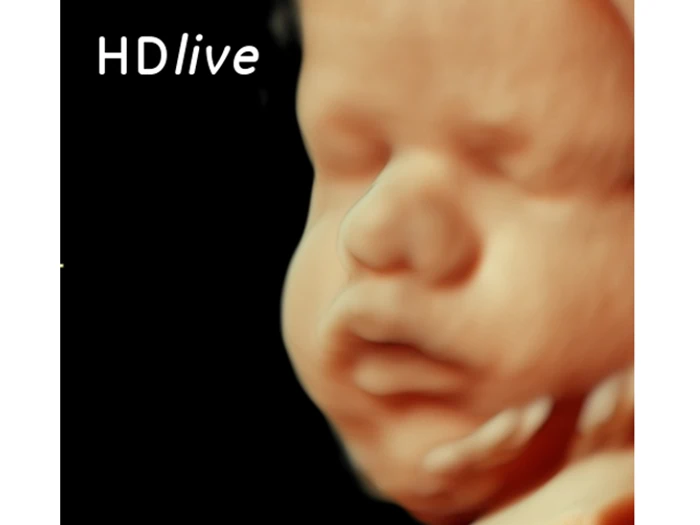

Ved 3D/4D scanning fornemmes den tredje dimension - dybde. Dette gør, at du oplever at få billeder, der i langt højere grad svarer til at se dit barn i virkeligheden end ved de almindelige 2D scanninger. Ved en scanning i 3D kan man virkelig få et indtryk af, hvordan ens barn ser ud med fine detaljer og personlige træk. Den fjerde dimension betyder, at der er bevægelser med, altså at du ser dit barn "live" i 3D. Ligger barnet i en god position for, at vi kan se ansigtet, vil det være muligt at se, hvis barnet fx smiler, smasker, gaber eller sutter på sine fingre.

3D/4D scanning er blevet utrolig populær, og vi kan med højt uddannet og trænet personale, samt scanningsudstyr med nyeste teknologi, præstere billeder og sekvenser i topklasse.

Herefter går vi over i 3D/4D scanning, hvor vi finder de helt rigtige scanningsvinkler for at kunne frembringe de helt optimale billeder og sekvenser.